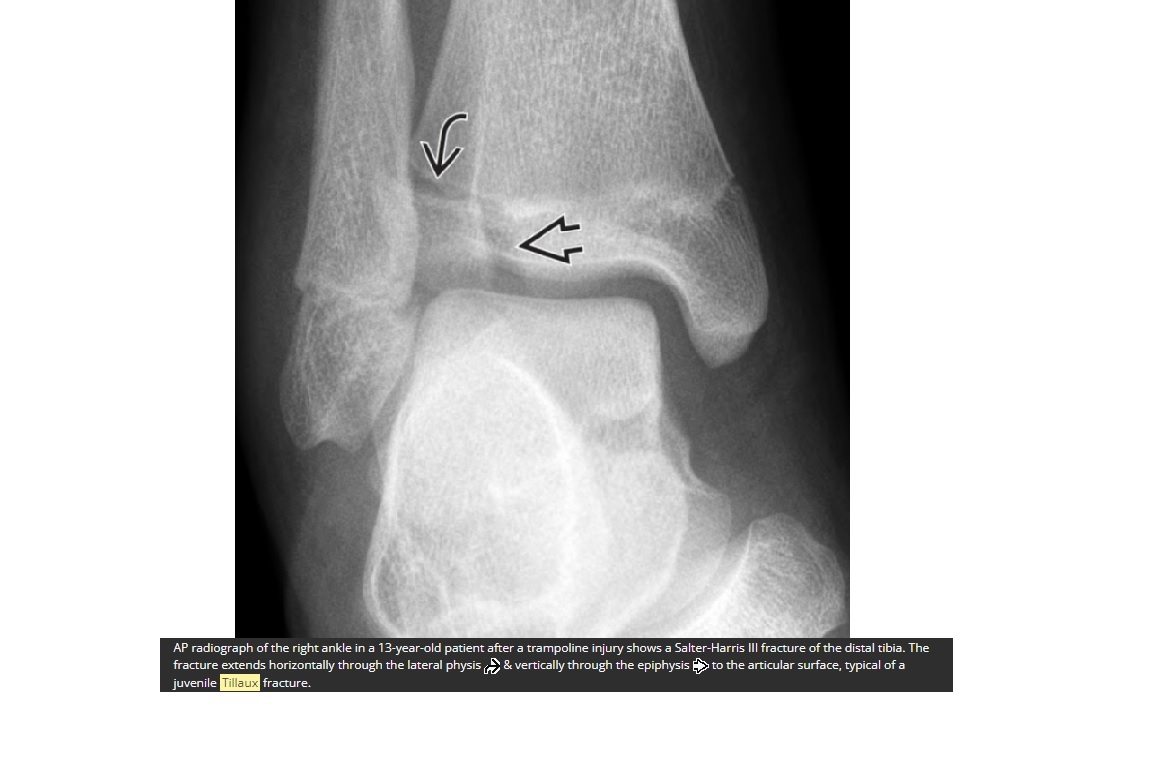

Tillaux fracture

Salter-Harris 3 = through the anterolateral distal tibial epiphysis